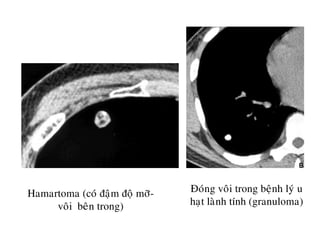

HAMARTOMA

Hamartoma (coù ñaäm ñoä môõ-

voâi beân trong)

Ñoùng voâi trong beänh lyù u

haït laønh tính (granuloma)